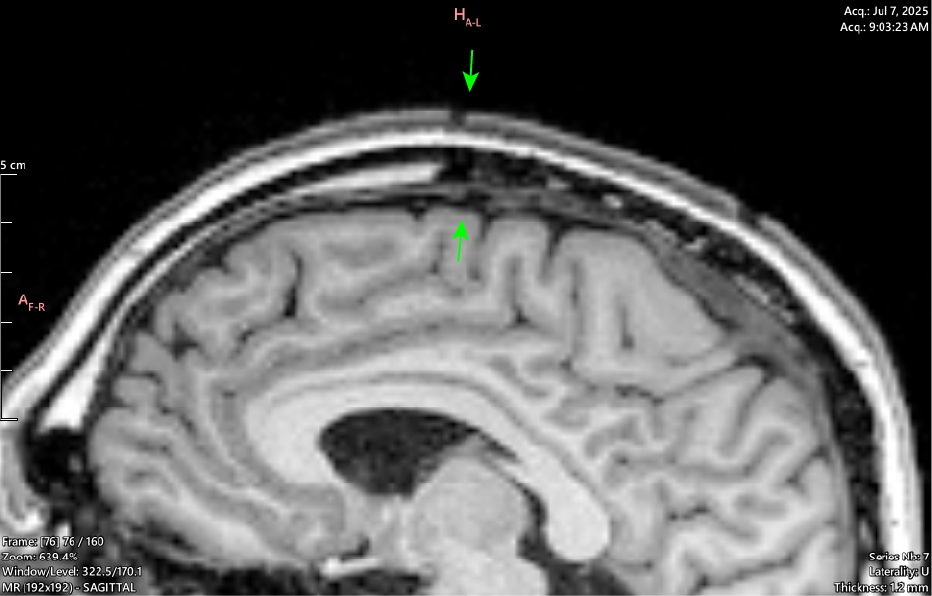

T1 Coronal

Coronal view shows this is happening along the Sagittal Suture - cranial sutures should return a uniform signal void (black) across all sequences as they are dense structures with little to no free water movement.

It can be seen throughout the JULY 2025 MRI series that a majority of the cranial sutures are instead filled with variable hypointense signaling describing dense, fibrous tissue.

By the age of 33 the cranial sutures should be almost - if not entirely - fused, showing as a thin (approx. 2mm) black zig-zag along their respective paths, if showing at all.

My Sagittal Suture in these images shows as 12.4mm wide at the outside margin, clearly showing atypical imaging presentation, indicating an underlying process occurring.